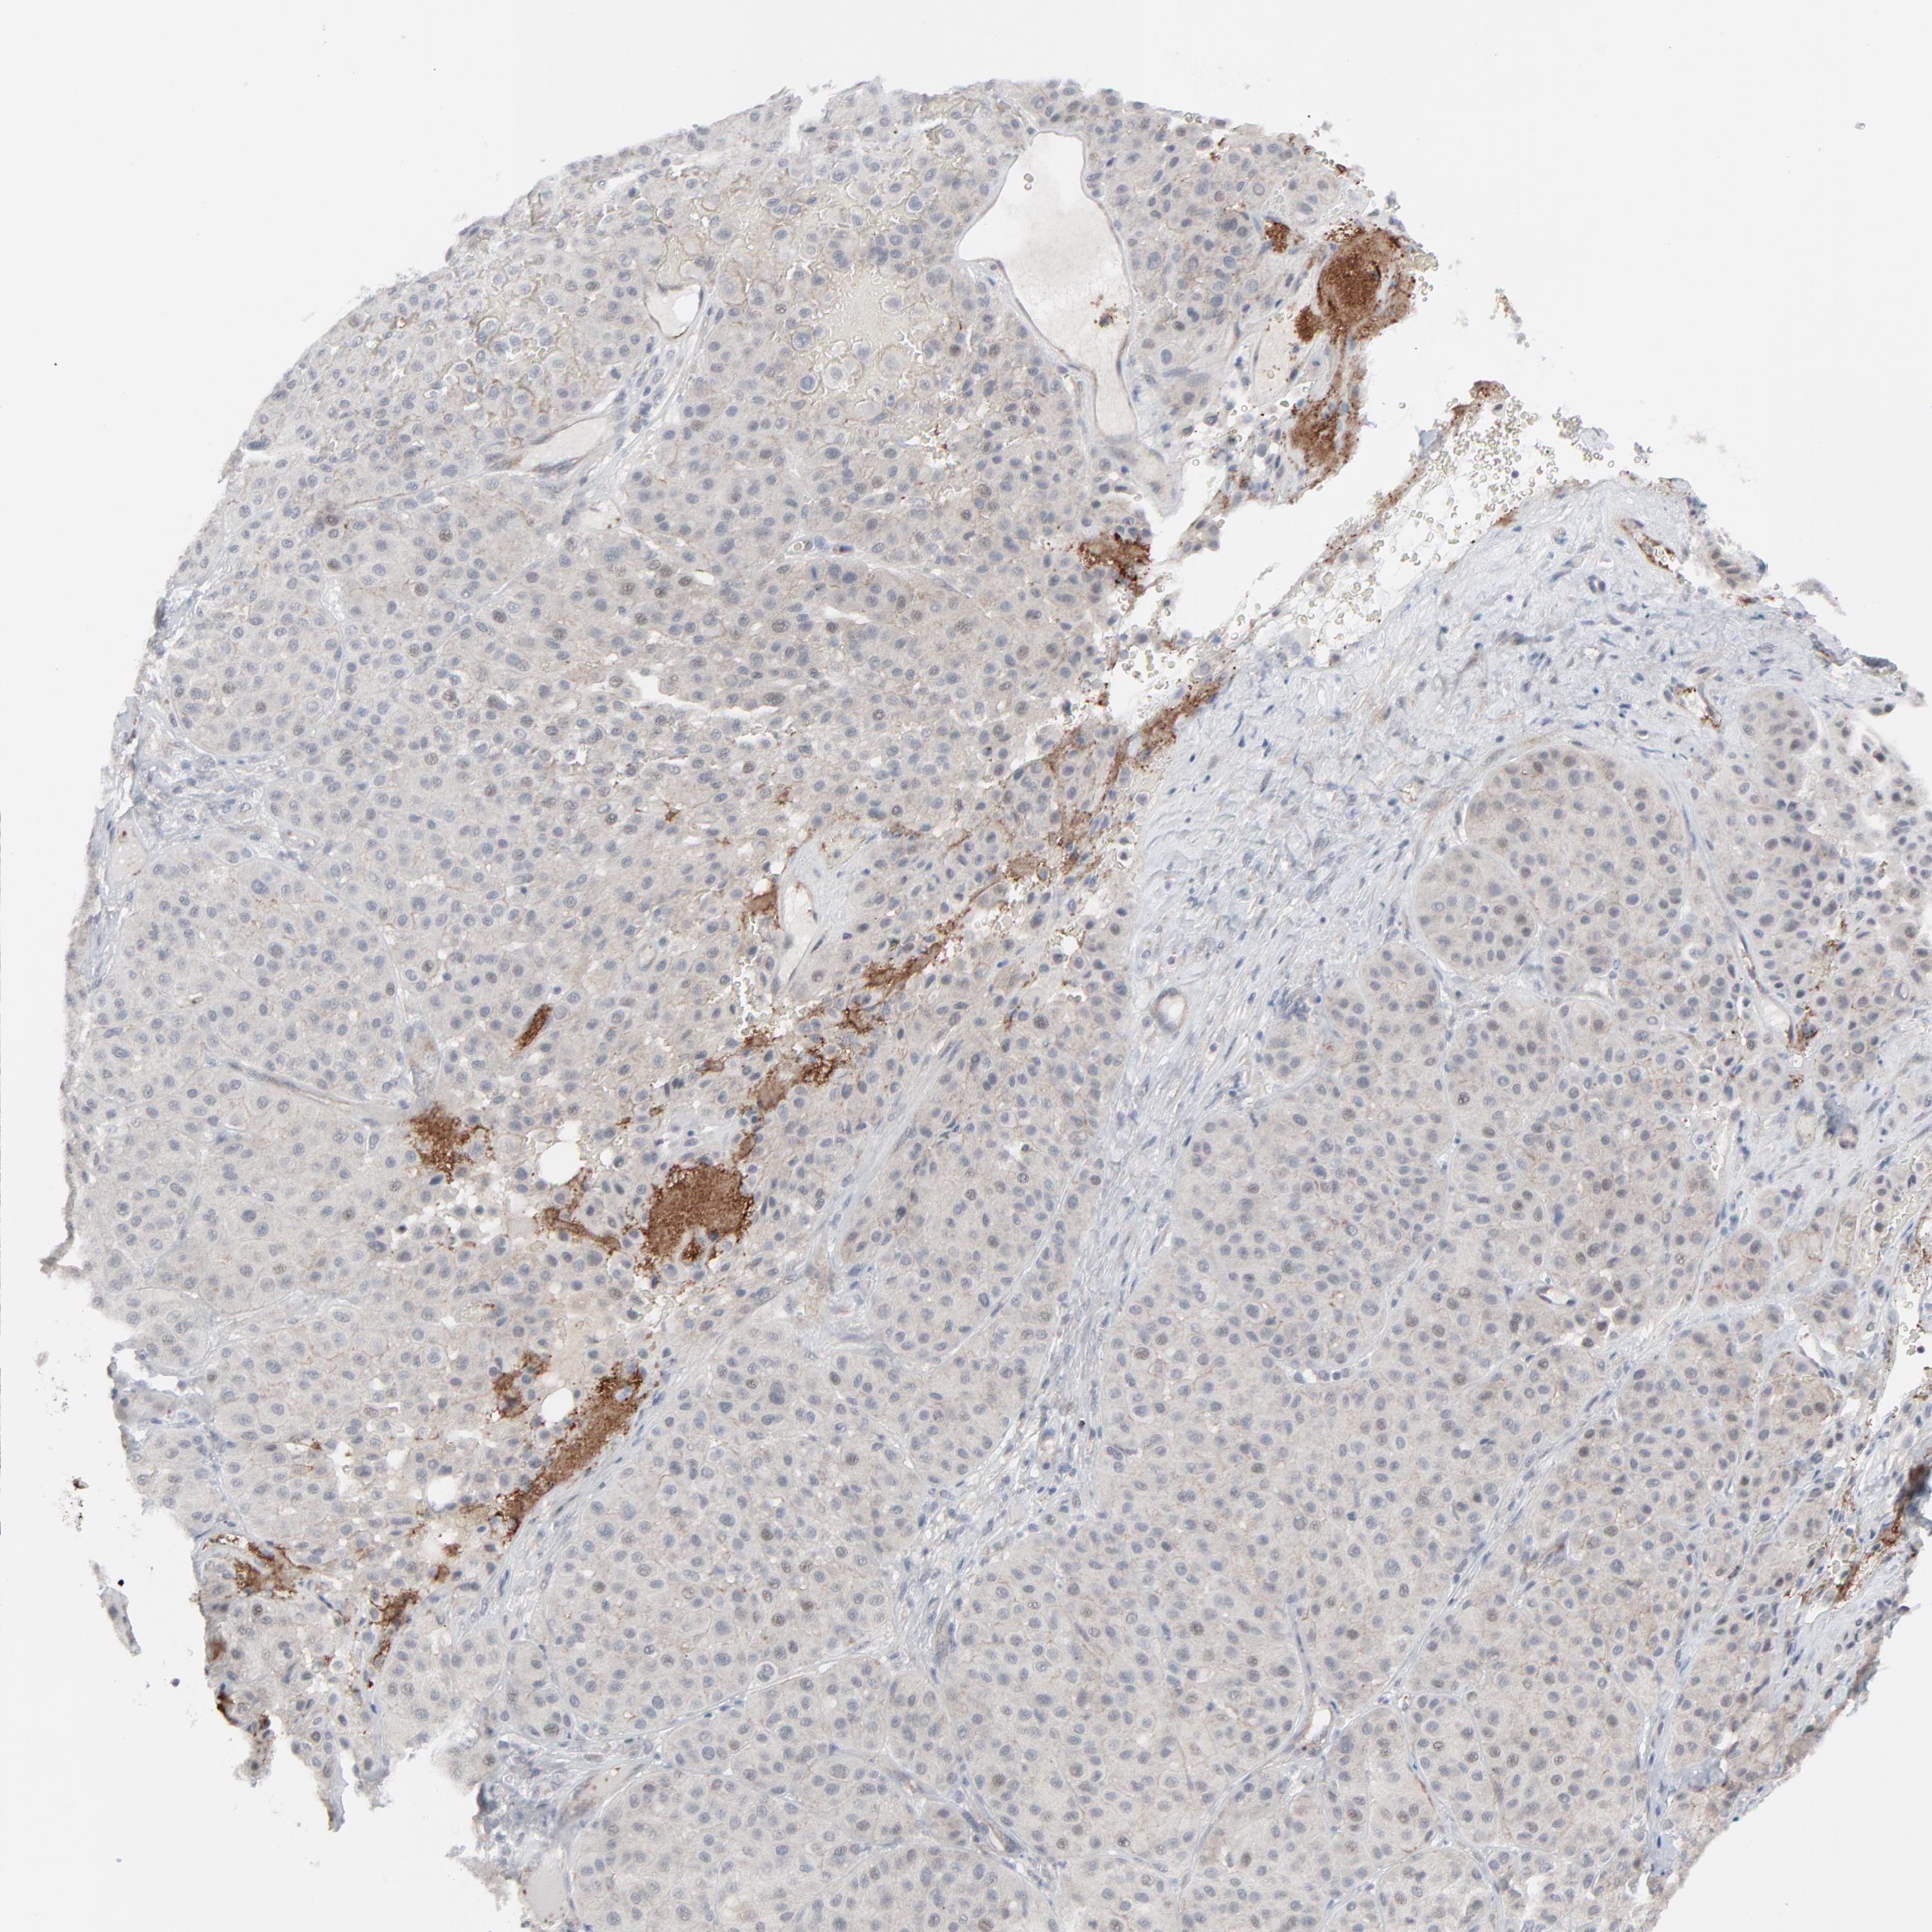

MELANOMA - Protein expressioni

A mouse-over function shows sample information and annotation data. Click on an image to view it in a full screen mode. Samples can be filtered based on level of antibody staining by selecting one or several of the following categories: high, medium, low and not detected. The assay and annotation is described here.

Note that samples used for immunohistochemistry by the Human Protein Atlas do not correspond to samples in the TCGA dataset.

Antibody stainingi

Antibody staining in the annotated cell types in the current human tissue is reported as not detected, low, medium, or high, based on conventional immunohistochemistry profiling in selected tissues. This score is based on the combination of the staining intensity and fraction of stained cells.

Each image is clickable and will lead to virtual microscopy that enables deeper exploration of all samples and also displays staining intensity scores, fraction scores and subcellular localization as well as patient and tissue information for each sample.

Antibody HPA003278

Antibody CAB022450

Staining

High

Medium

Low

Not detected

Intensity

Strong

Moderate

Weak

Negative

Quantity

>75%

75%-25%

<25%

None

Location

Nuclear

Cytoplasmic/membranous

Cytoplasmic/membranous,nuclear

Malignant melanoma, NOS

Malignant melanoma, Metastatic site